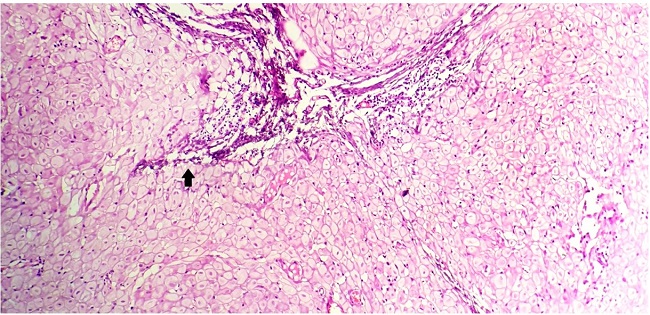

On microscopic evaluation, hematoxylin and eosin (H&E) stained sections revealed multiple nodules composed of decidualized stromal cells surrounding a few slit-like endometrial glands with fibroblasts and collagen (Figure 1).

These decidual cells were polygonal, with large nuclei, abundant homogenous eosinophilic cytoplasm (Figure 2), and associated with vacuolar degeneration in some places.

Occasional dilated endometrial glands were also noted, which showed eosinophilic secretions with adipose tissue present along the periphery (Figure 3). No features depicting atypia were noted.